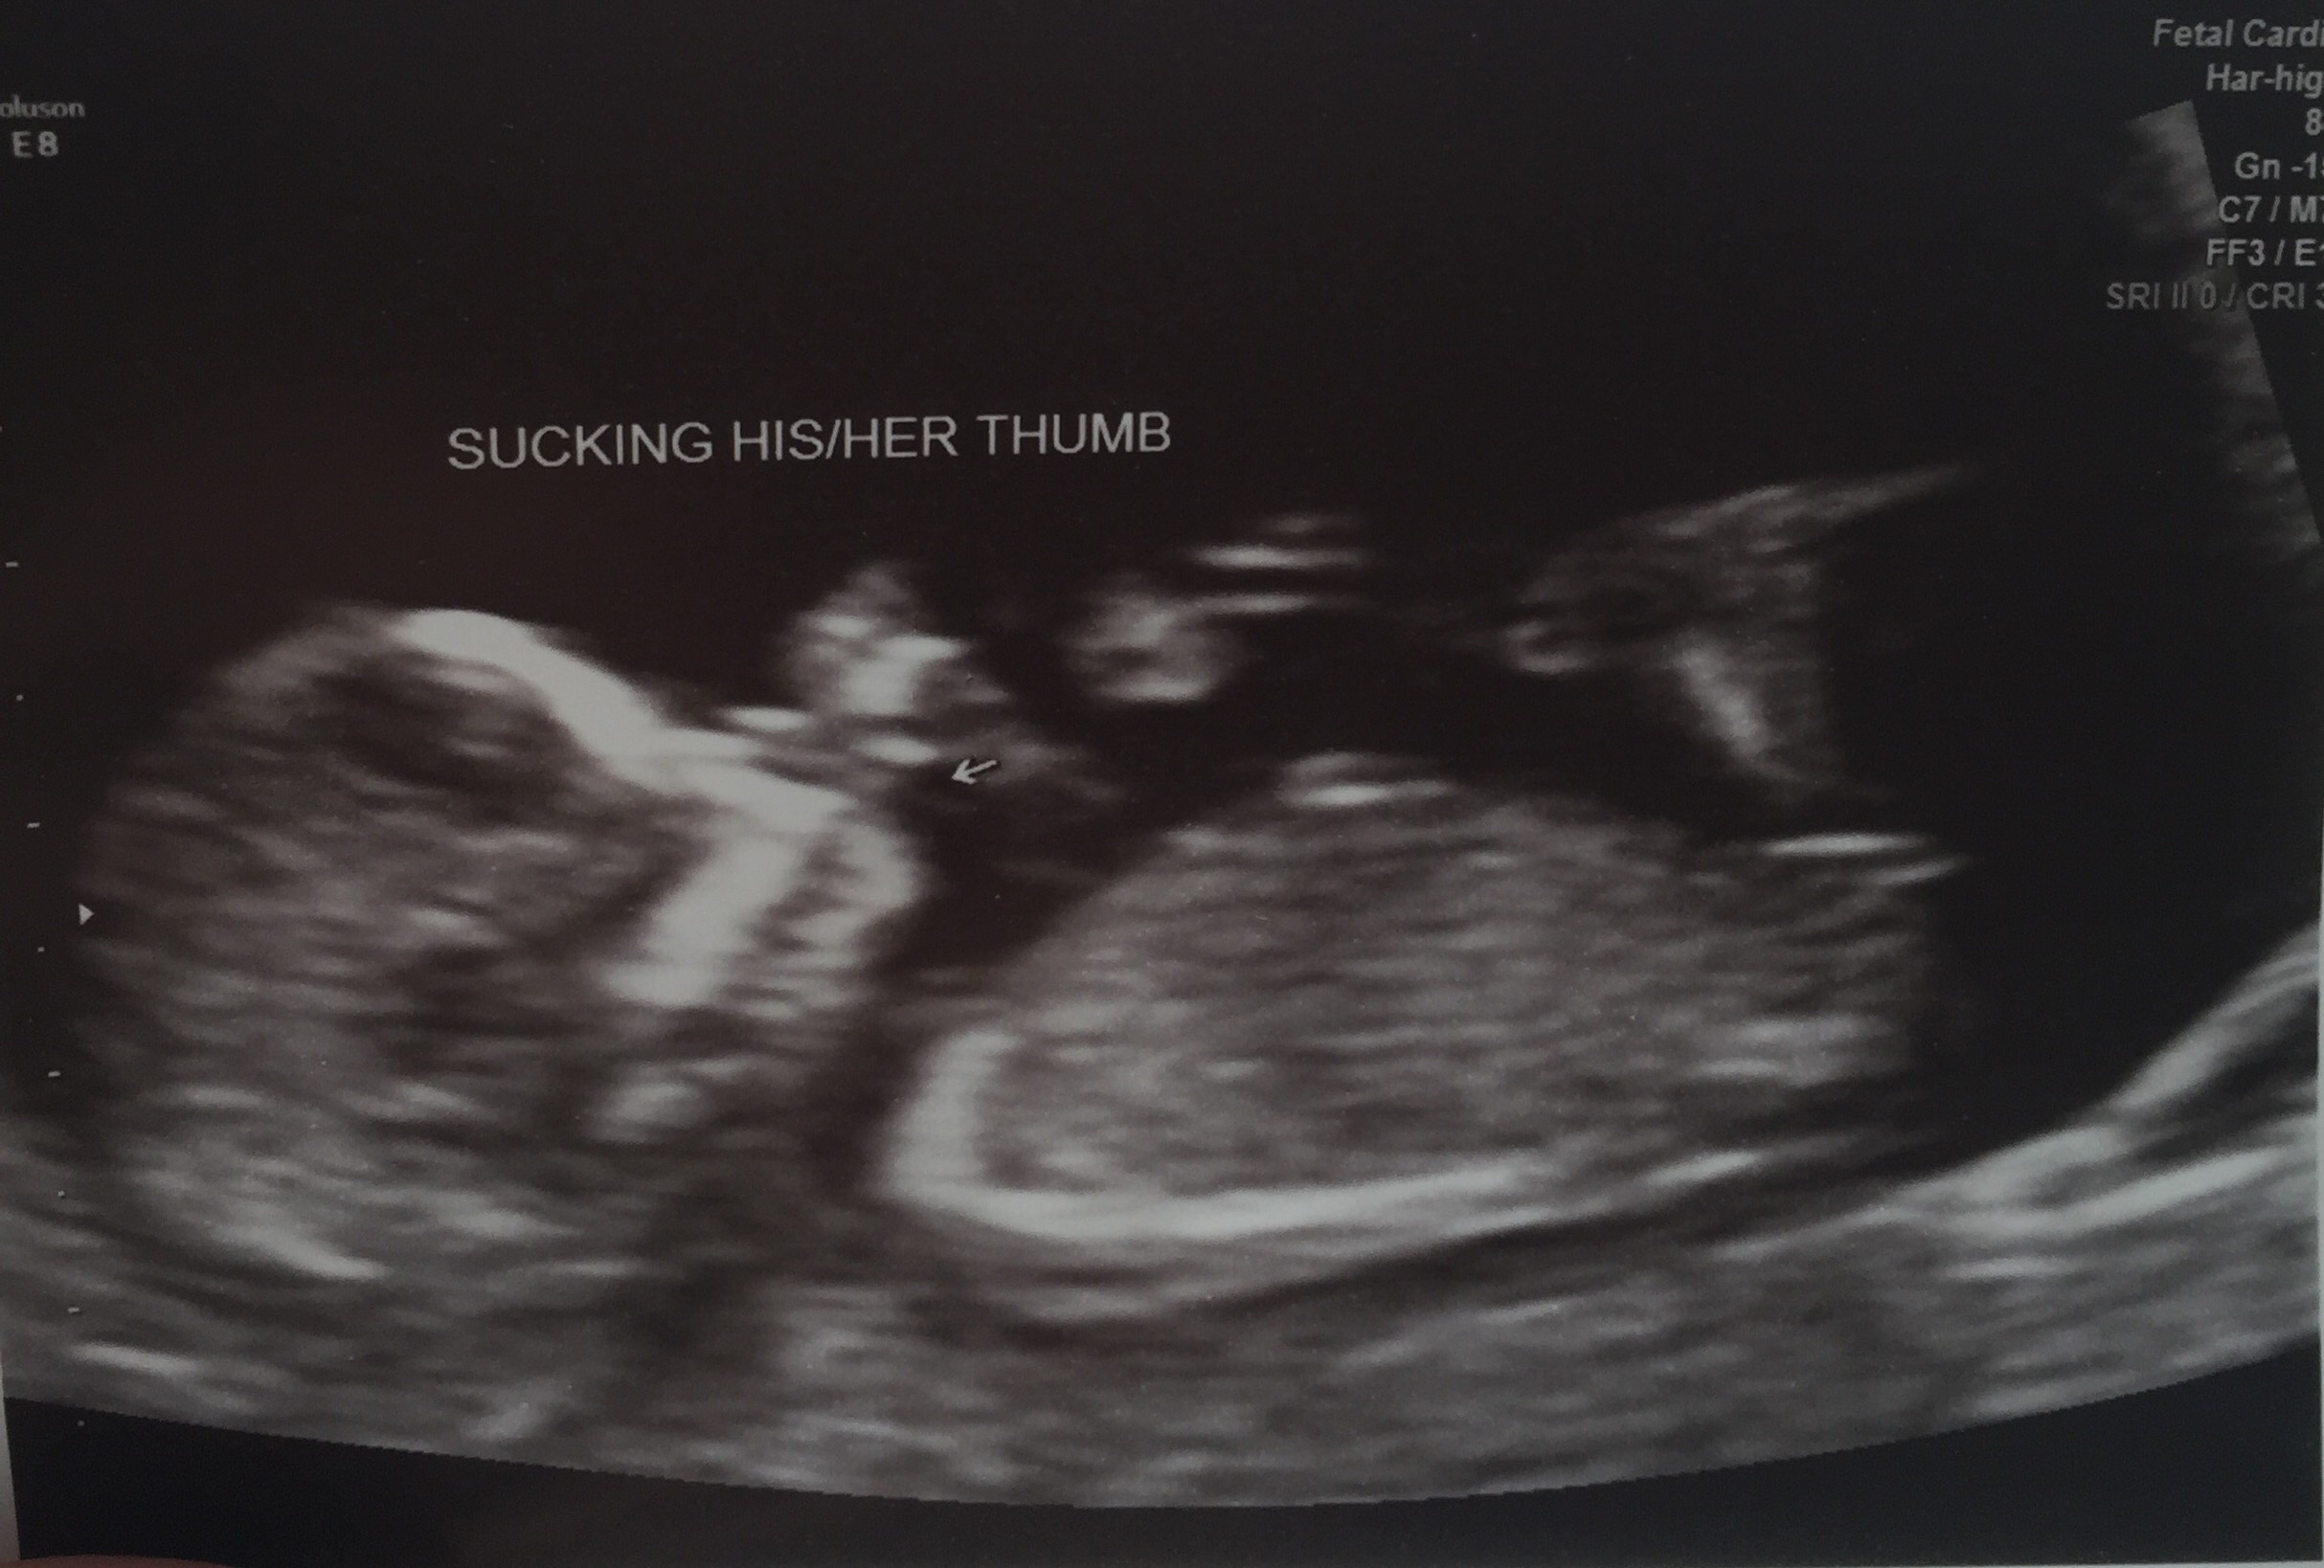

Looks girly to me!!

Pink.. Congratulations

girl

Girly!